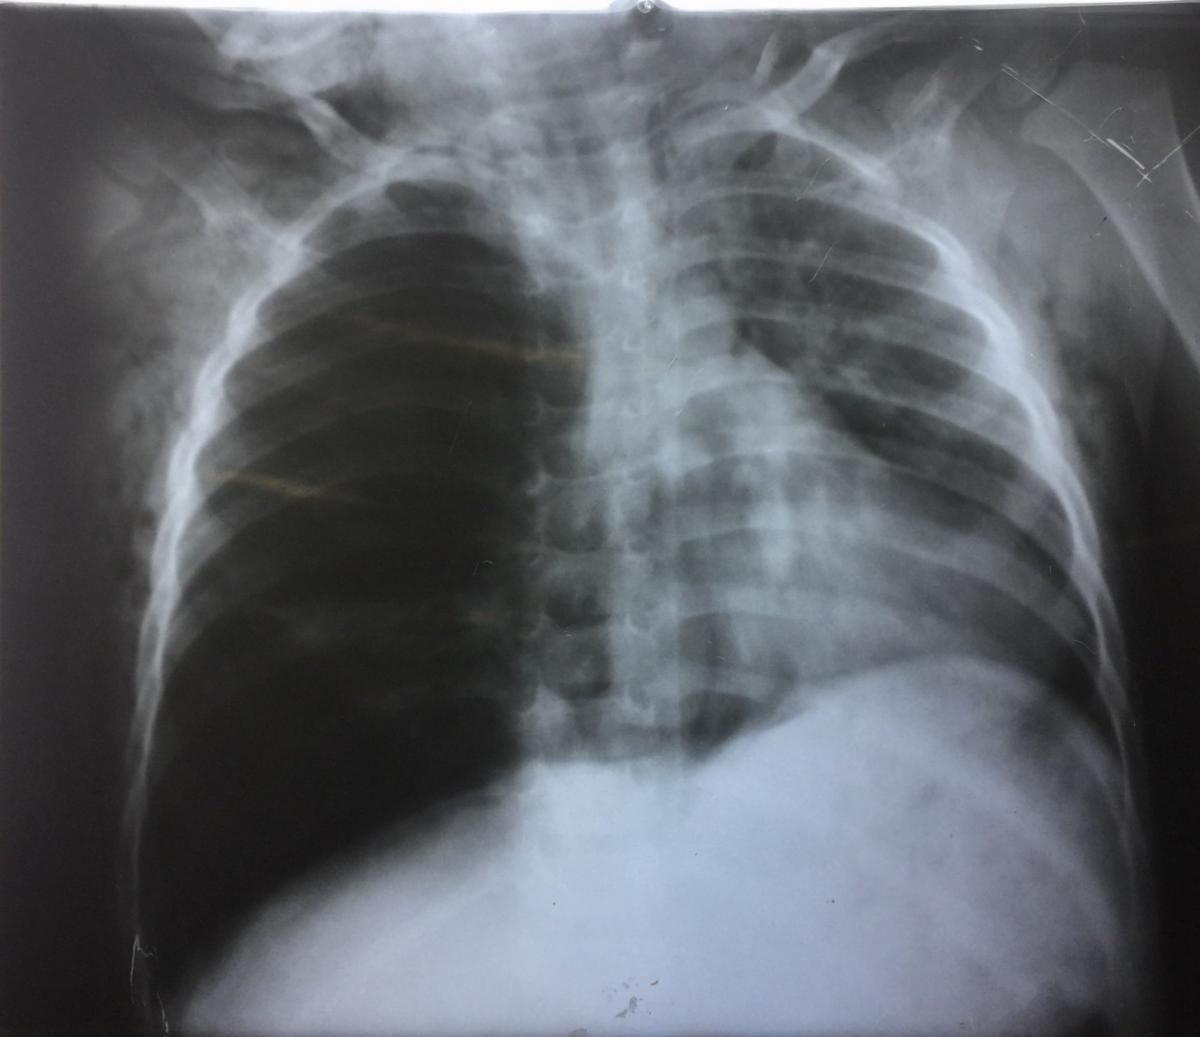

Pulmonary actinomycosis presenting as postobstructive pneumonia

From www.ijidonline.com

Pulmonary actinomycosis presenting as postobstructive pneumonia What Does Decreased Air Entry Mean Web using a stethoscope, the health care provider may hear normal breathing sounds, decreased or absent breath sounds, and. Web reduced intensity (decreased air entry) muffled breath sounds as a result of pleural effusion, pneumonia, chronic obstructive. Swelling, blockages or mucus in your. Web abnormal breath sounds may indicate a respiratory illness, heart disease, infection, or other problems. Web air. What Does Decreased Air Entry Mean.